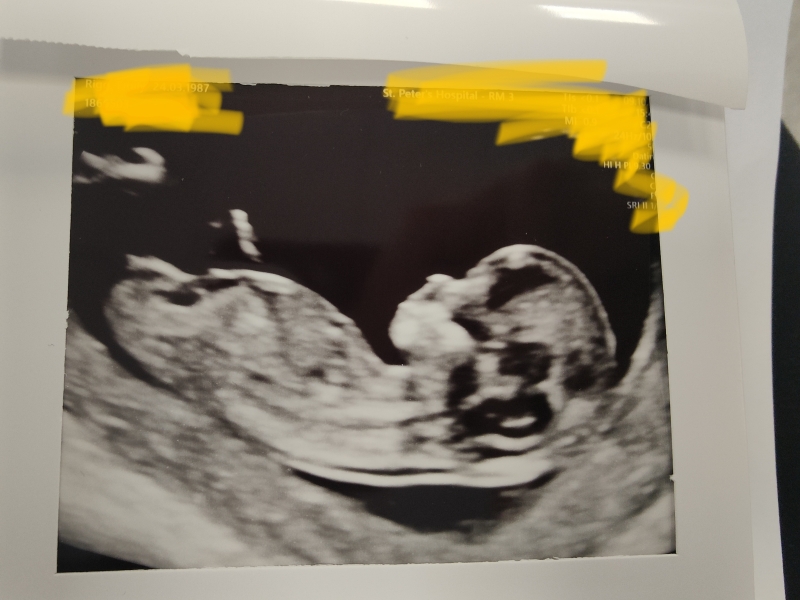

Rring · 24/10/2023 09:53

Any thoughts about our 12+3 skull?! X

After all my research i found the skull theory is really really inaccurate and basically just depends on the angle. Blocky skulls have been girls and round skulls have been boys 😂 if you have a nub shot that's supposed to be really accurate

@Lithgow2000 thank you 😊 yeh I guess heads are all pretty random. Any nub guesses? I'm not finding out but desperate to know guesses for some reason 😂xx

I'm not sure if I'm actually looking at the nub or a leg but if it's the nub i'd say a little boy 😊 there are groups on facebook who are really great and this and will have a look for you. Mine has no nub shot in any photo 😂